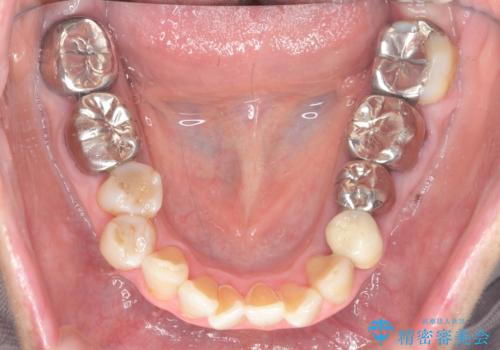

- 見た目の悪い銀歯や虫歯、歯の欠損、全体的な治療を希望されて来院されました。

インプラント治療や根管治療・セラミック治療を総合的に考えた精度の高い治療を計画し、しっかり噛めるようになるのはもちろん長期的な予後や審美性の向上を考えた全顎的な治療を実践していきます。

期間は約2年ほどかかりましたが、審美的な仕上がりとともに清掃のしやすさも非常に満足いただくことができました。